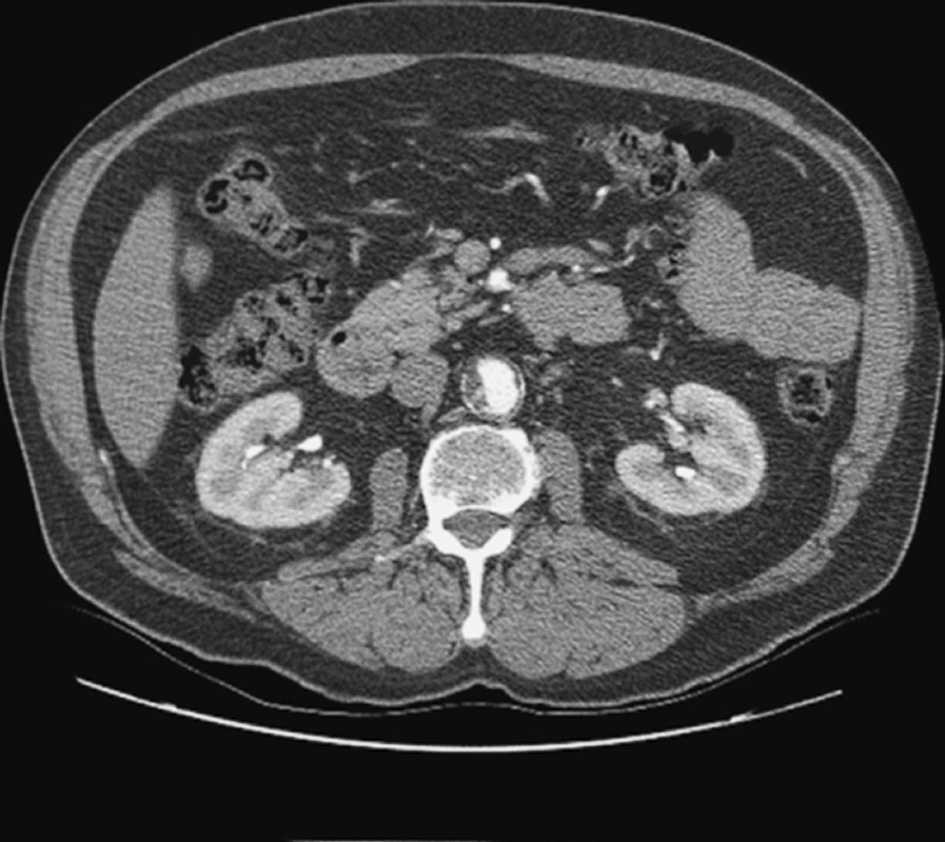

Todos los pacientes fueron reevaluados sistemáticamente mediante angiografía con tomografía computarizada (TC) abdominal y, en algunos casos, mediante aortografía (n = 18). El cuello aórtico adverso se definió como la existencia de angulación intensa (> 60°), cuello corto (< 15 mm), calcificación importante o presencia de trombo circunferencial. La anatomía adversa del cuello aórtico contraindicó en términos generales la realización de la REVA y llevó a considerar la cirugía abierta (figs. 2 y 3). La característica morfológica que impidió con mayor frecuencia la realización de un procedimiento endovascular fue el cuello aórtico corto (tabla II). En los pacientes considerados desde el punto de vista fisiológico poco idóneos para la cirugía abierta, la REVA fue una opción terapéutica a pesar de la anatomía adversa del cuello aórtico. La selección del abordaje transperitoneal o retroperitoneal en la cohorte de estudio con un cuello aórtico adverso quedó a criterio del cirujano. Las intervenciones fueron realizadas por siete cirujanos distintos durante el período de estudio. Fueron excluidos los pacientes con AAA suprarrenal, toracoabdominal o roto.

Fig. 3. Aneurisma aórtico infrarrenal con un trombo circunferencial en la parte proximal del cuello, inmediatamente por debajo de las arterias renales.